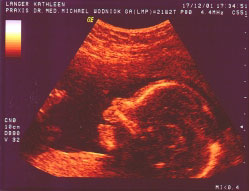

Über dieses Bild freuen sich meine Eltern besonders. Es ist auch vom 17.12.2001.

Könnt Ihr es sehen? Ich war ganz lieb und habe gelächelt. Der Onkel Doktor meinte, es wäre sehr selten, daß man das lachen sieht und es dann auch noch ein Foto davon bekommt. Mama und Papa sind gleich mächtig stolz darauf. Das Bild ist bunt, weil meine Eltern ein besonderes Ultraschall von mir haben machen lassen. Es hieß Doppler-Sonografie. Dabei kann der Okel Doktor wohl erkennen ob ich mich auch wirklich gut entwickele oder vielleicht krank bin. Aber ich glaube, er war zufrieden mit mir...